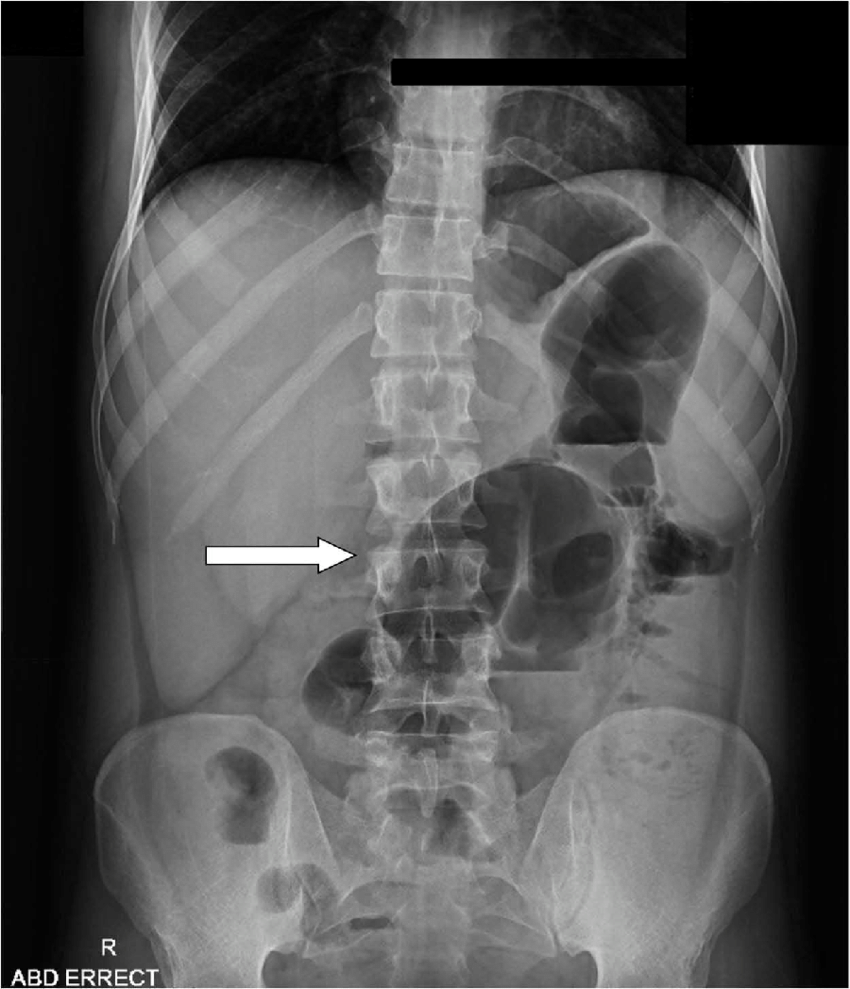

"Coffee Bean" sign on abdominal x-ray in a patient with Sigmoid Volvulus

Coffee Bean